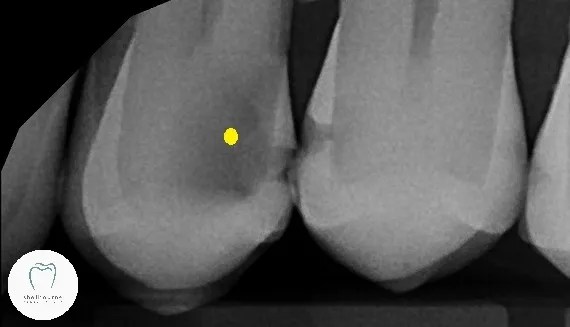

The (new) patient had come in for an exam a few weeks ago, and as part of his examination we took some X-rays. One of the things we found was this:

Both teeth are damaged here, but the one to the left has a big cavity. (Yellow dot) That’s getting worryingly close to the nerve. If the decay reaches the nerve it dies, and we have to do root canal. This is definitely filed under “urgent”.

Incidentally this tooth wasn’t causing any pain or discomfort at all. Sometimes people adopt a “If it’s not painful all must be well” attitude. Well, that’s a sure-fire way of ensuring you’ll get to do plenty of root canals! Luckily this gentleman had decided to attend before we got to that point.